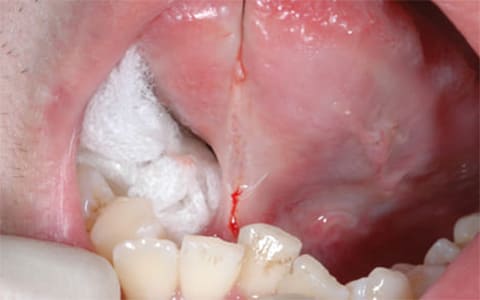

舌小帯の短縮を認める -

舌尖部に糸をかける